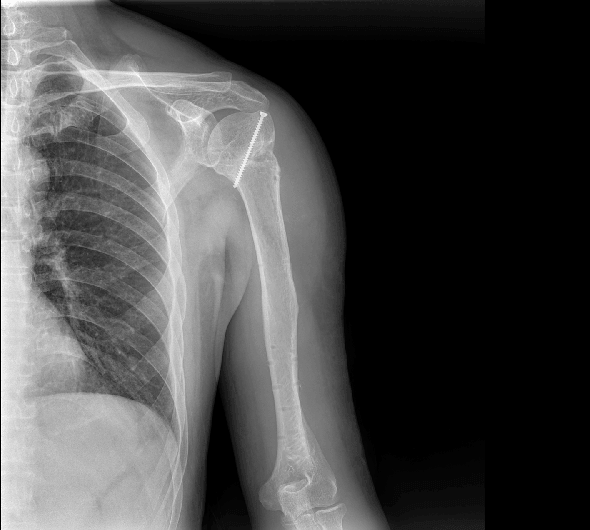

临床图像